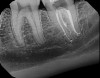

With this technology, gentle vortical flow is induced within the root canal system with a slight negative pressure at the apices, which reduces the potential for extrusion. The result is a more complete removal of pulp tissue, bacteria, and bacterial biofilm within the root canal, including debris in anatomically complex structures (eg, isthmi, lateral canals, multiple apical foramina).18-20 In other words, it can clean and disinfect even where a file or rotary instrument cannot reach (Figure 15 through Figure 18). All this is accomplished with minimal instrumentation, most of the time to a size as small as a .04 taper #15 or #20 rotary instrument. In addition, conservation of root dentin results in a stronger root, which may increase the survival rate of the treated tooth.7

Fig 15. Postoperative obturation radiographs after multisonic ultracleaning technology, revealing complex and intricate canal anatomy.

Figure 15

Fig 16. Postoperative obturation radiographs after multisonic ultracleaning technology, revealing complex and intricate canal anatomy.

Figure 16

Fig 17. Postoperative obturation radiographs after multisonic ultracleaning technology, revealing complex and intricate canal anatomy.

Figure 17

Fig 18. Postoperative obturation radiographs after multisonic ultracleaning technology, revealing complex and intricate canal anatomy.

Figure 18